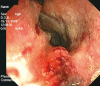

Patients with inflammatory bowel disease (IBD) are at increased risk of colorectal malignancies. Adenocarcinoma is the commonest type of colorectal neoplasm associated with ulcerative colitis (UC) and Crohn's disease, but other types of epithelial and non-epithelial tumors have also been described in inflamed bowel. With regards to non-epithelial malignancies, lymphomas and sarcomas represent the largest group of tumors reported in association with IBD, especially in immunosuppressed patients. Carcinoids and in particular neuroendocrine neoplasms other than carcinoids (NENs) are rare tumors and are infrequently described in the setting of IBD. Thus, this association requires further investigation. We report two cases of neoplasms arising in mild left-sided UC with immunohistochemical staining for neuroendocrine markers: a large cell and a small cell neuroendocrine carcinoma of the rectum. The two patients were different in age (35 years vs 77 years) and disease duration (11 years vs 27 years), and both had never received immunosuppressant drugs. Although the patients underwent regular endoscopic and histological follow-up, the two neoplasms were locally advanced at diagnosis. One of the two patients developed multiple liver metastases and died 15 mo after diagnosis. These findings confirm the aggressiveness and the poor prognosis of NENs compared to colorectal adenocarcinoma. While carcinoids seem to be coincidentally associated with IBD, NENs may also arise in this setting. In fact, long-standing inflammation could be directly responsible for the development of pancellular dysplasia involving epithelial, goblet, Paneth and neuroendocrine cells. It has yet to be established which IBD patients have a higher risk of developing NENs.